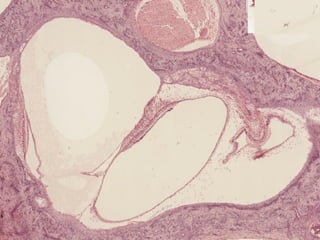

Laberintos Óseos

Laberinto

Membranoso

Utrículo

Macula del

Saculo

Conductos Semicirculares

Espacio con

Perilinfa

Endolinfa